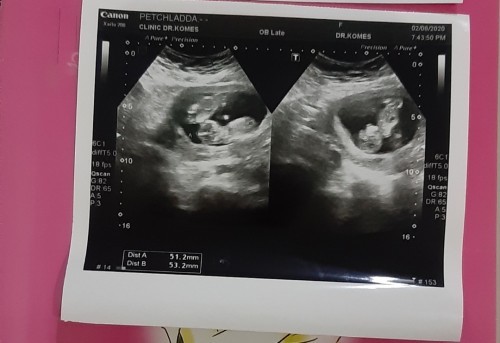

มีใครท้องแฝดบ้างค่ะขอดูรูปอัลตร้าซาวแม่ๆท้องแฝดหน่อยค่ะ ขอบคุณค่ะ